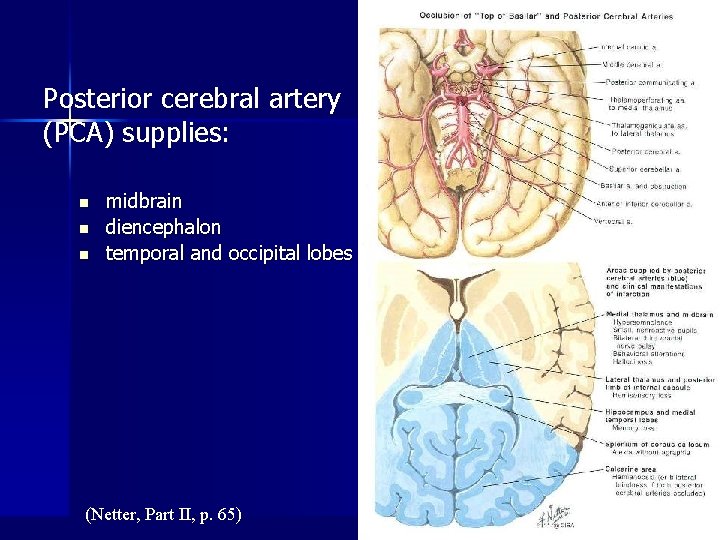

Posterior cerebral artery (PCA) supplies: n n n midbrain diencephalon temporal and occipital lobes (Netter, Part II, p. 65)